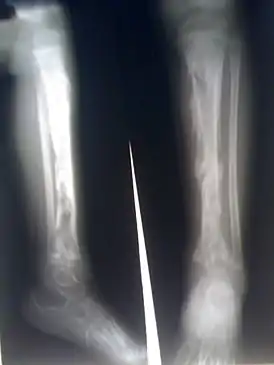

![]() Остеомиелит большеберцовой кости | |